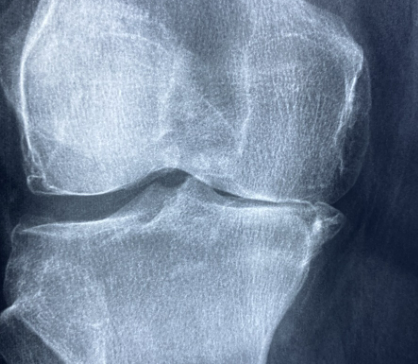

여러분, 무릎이 찌릿하고 계단 오를 때 ‘아이고~’ 소리가 절로 나온 적 있으신가요? 저도 50대를 넘어서면서부터 무릎이 조금씩 좋지 않다고 많이 느끼고 있습니다. 특히 등산을 좋아합니다. 무릎 연골이 빨리 닳을 수 밖에 없는 취미를 하고 있었던 것이죠. 더욱 그래서 요즘 ‘관절 건강’에 많은 관심을 가지게 되었습니다. 그러다가 우연히 TV 건강프로그램에서 알게 된 게 바로 철갑상어 콘드로이친입니다. 집에도 이미 이전에 구입해 놓은 콘드로이친이 있어서 콘드로이친이 다 똑같은 것으로만 알았는데 어디서 추출한 것이냐에 따라 성분과 효과가 다르다는 것을 알게 되었죠.

콘드로이친은 원래 우리 몸속 연골, 힘줄, 인대 등에 존재하는 천연 성분입니다. 쉽게 말해 관절 사이에서 뼈끼리 부딪히지 않도록 완충 역할을 해주는 거죠. 그런데 나이가 들거나 운동을 과하게 하면 이 성분이 줄어들면서 관절 마찰이 생기고 통증이 시작됩니다. 그래서 요즘 관절 영양제엔 콘드로이친이 빠지지 않고 들어갑니다. TV를 보면 하루에 한 두번은 이 콘드로이친 광고를 접하는 것 같습니다.